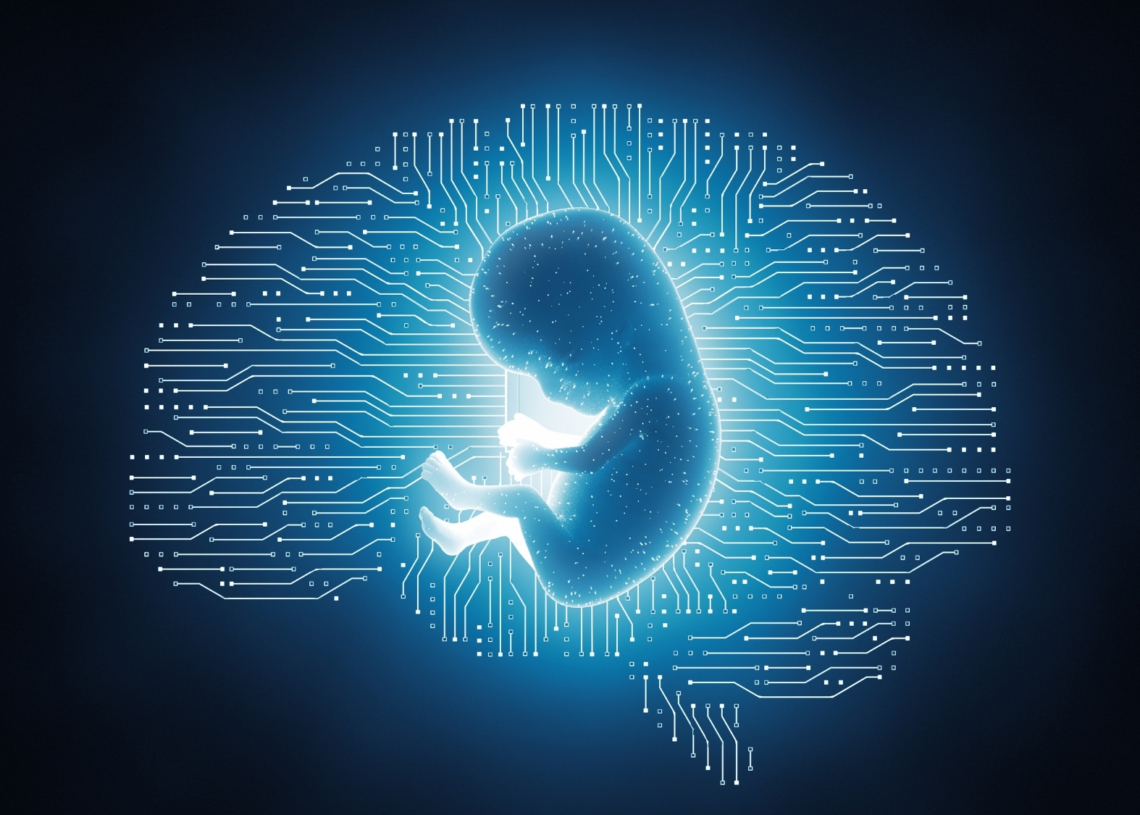

In another example of a tech startup’s founders ignoring the ethical lessons of sci-fi movies and books and instead becoming enamored of the society-ruining technologies the stories are about, Wired recently reported that a startup called R3 Bio is testing the idea of cloning brainless human bodies for organ transplants.

Publicly, the company is pitching the concept with a truly horrifying set of words that sound like the street slang from a cyberpunk novel but is now being used as official corporate lingo: organ sacks, or, what are essentially lab-grown bodies without brains, designed explicitly to produce organs for transplant or serve as more ethical alternatives to animal testing.

These sacks of human meat and parts would contain functioning organ systems but lack any capacity for thought or pain, as if that makes it any better. The idea here is that in a world where hundreds of thousands of Americans are waiting for transplants every day, why not just grow replacement organs instead of waiting for donors?